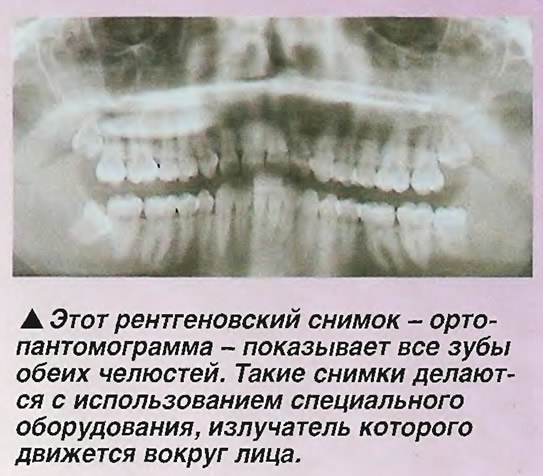

Стоматологические Исследования: Рентген Инвагинации Зубов